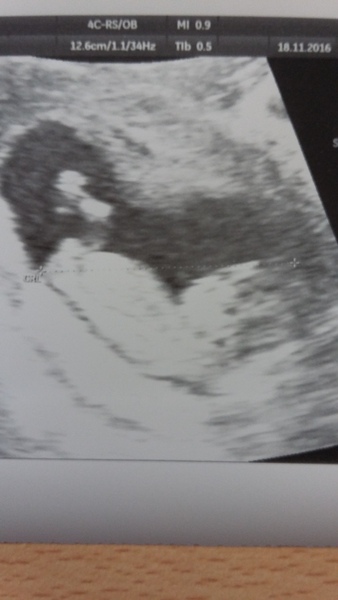

haveacupoftea · 18/11/2016 13:41

One bouncing baby! Back to my original EDD of 2nd June Smile

11+6